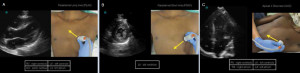

Appropriate probe positioning and corresponding ultrasound image of A) PLAX, B) PSAX, and C) A4C.